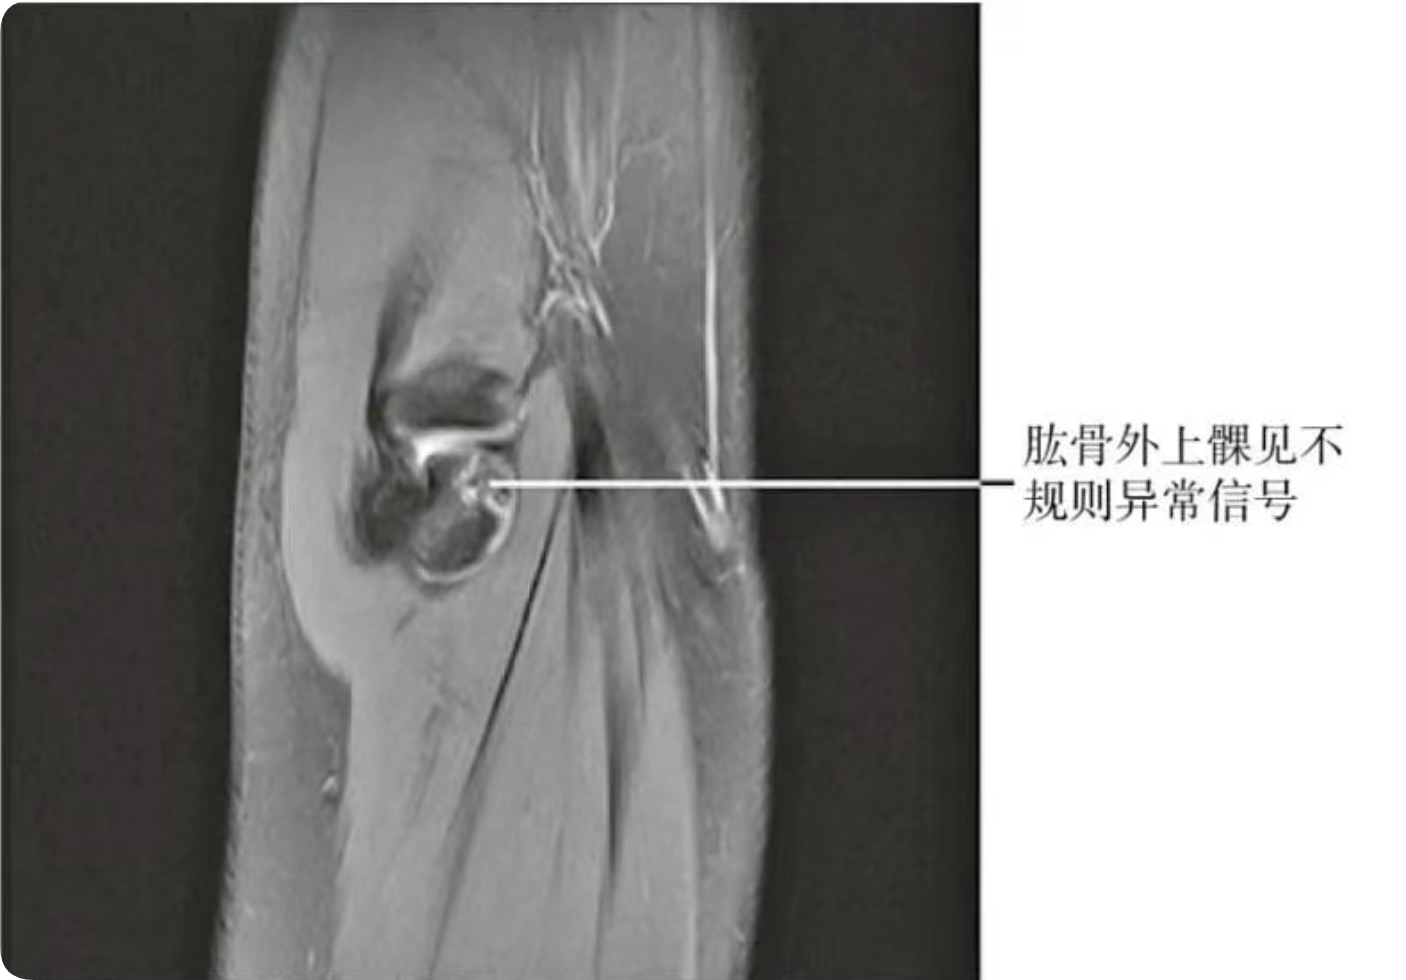

【MRI检查】

可见异常信号。(图2)

图2 肱骨外上髁MRI片